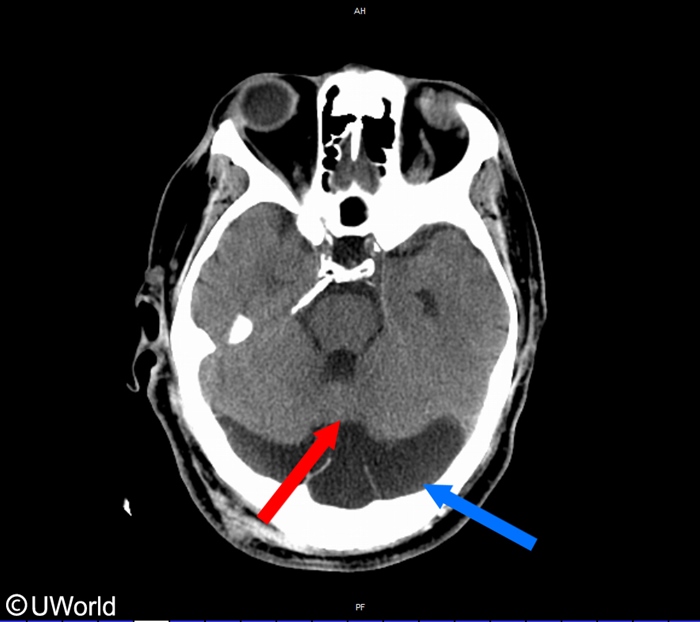

Dandy Walker

This child likely has Dandy-Walker malformation, a developmental anomaly characterized byhypoplasia/absence of the cerebellar vermis (red arrow) and cystic dilation of the fourth ventricle with posterior fossa enlargement (blue arrow).

Patients often present during infancy with developmental delay and progressive skull enlargement. Cerebellar dysfunction can result in unsteadiness and impaired muscle coordination. Non-communicating hydrocephalus may occur due to atresia of the foramina of Luschka and Magendie, resulting in symptoms of elevated intracranial pressure (eg, irritability, vomiting). Other associated features can include agenesis of the corpus callosum and malformations involving the face, heart, or limbs.